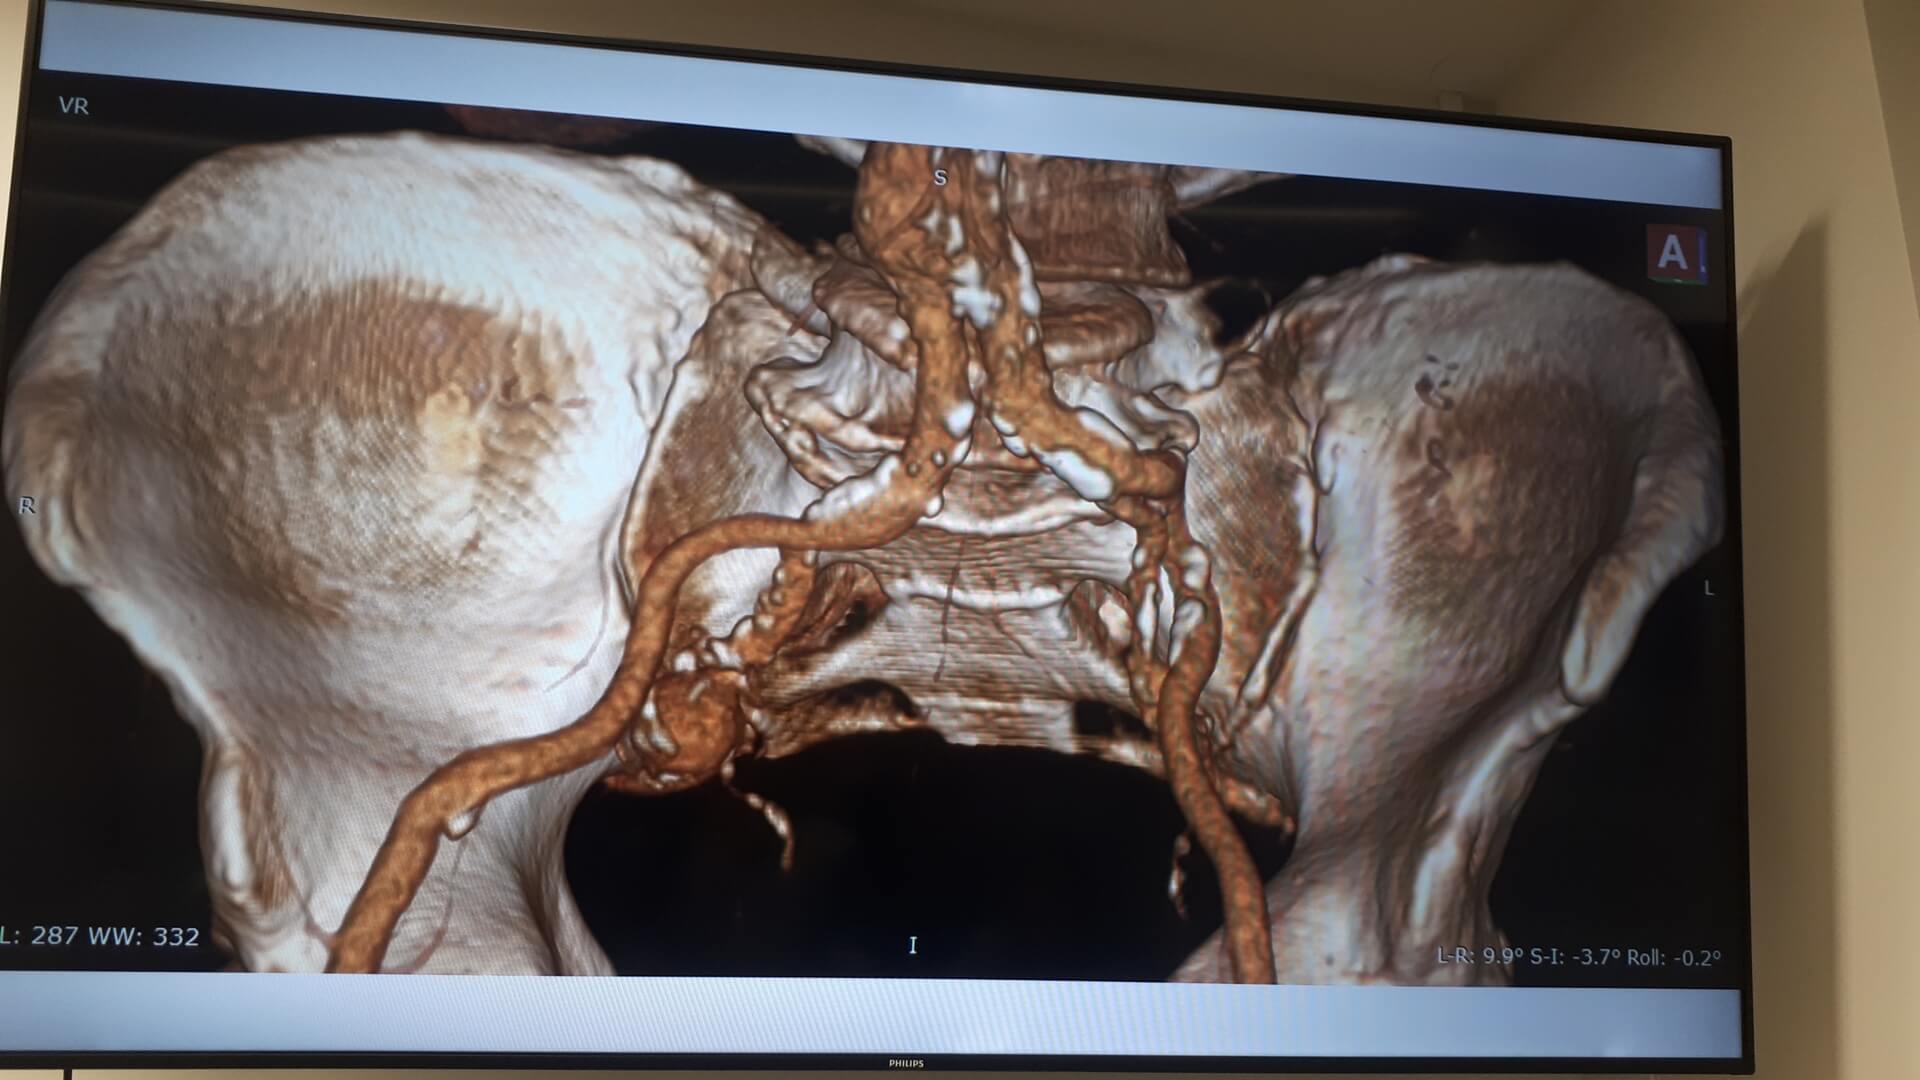

Pierwszą w Polsce operację wszczepienia nowego rodzaju stentgraftu, czyli specjalnej protezy do zabezpieczania tętniaków aorty, przeprowadzili lekarze z Uniwersyteckiego Szpitala Klinicznego w Białymstoku.

Chodziło o tętniaka tętnicy biodrowej u 64-letniego pacjenta. Operację przeprowadzono w minioną środę (10.04) w Klinice Chirurgii Naczyń i Transplantacji USK. Pacjent czuje się dobrze i niedługo wychodzi ze szpitala.

Jak mówił w czwartek (11.04) na konferencji prasowej kierownik tej kliniki dr hab. Jerzy Głowiński, tętniak miał prawie 4 cm, co w relacji do wielkości tętnicy biodrowej wewnętrznej stanowiło duże zagrożenie, bo w każdej chwili ścianki naczynia krwionośnego mogły pęknąć, powodując – zagrażający życiu – krwotok wewnętrzny. - Możliwości uratowania byłyby naprawdę znikome – powiedział.

W przypadku tego chorego nie wchodziła w grę klasyczna operacja, bo tętniak znajdował się zbyt głęboko, by był możliwy do niego dostęp chirurgiczny. Dotąd zasadą postępowania w takiej sytuacji było podwiązywanie lub wyłączanie tętnicy (klejem lub specjalnymi spiralami). Dr Głowiński zwrócił uwagę, że choć ta tętnica nie ratuje życia, to poprawia komfort pacjenta, bo odpowiada za ukrwienie narządów jamy brzusznej oraz – co istotne jest u mężczyzn – za prawidłową erekcję.

Rozwiązaniem okazał się nowy rodzaj stentgraftu, czyli specjalnej protezy wszczepianej do tętnic. "Jest to stentgraft, który jest jednocześnie i miękki, i na tyle sztywny, że się do tego celu dobrze nadawał" – powiedział. Zwrócił przy tym uwagę, że stosowane już standardowo stentgrafty są albo sztywne, albo elastyczne i do zabezpieczenia tętniaka w takim miejscu się nie nadawały.

DrJerzy Głowiński wyjaśniał, że tętnica biodrowa jest stosunkowo mała i kręta, do tego jej średnica nie jest na całej długości taka sama. Nowy rodzaj stentgraftu składającego się z pierścieni naprzemiennie sztywnych i elastycznych dał możliwość "domodelowania" go w taki sposób, by na całym zabezpieczanym tętnicy odcinku był właściwie zainstalowany.

Do tego od wewnątrz stentgraft jest pokryty heparyną, co ma zapewnić jego długotrwałą drożność i zapobieganie zakrzepicy. - Zakładamy, że stentgraft posłuży pacjentowi również na długie lata – dodał kierownik Kliniki Chirurgii Naczyń i Transplantacji USK w Białymstoku. Przyznał, że takie umiejscowienie tętniaka jest rzadkie, w statystykach białostockiej kliniki trafia się 2-3 razy do roku. Zoperowany z użyciem nowego rodzaju stentgraftu pacjent czekał na to dwa miesiące. Sama proteza kosztuje ok. 9-10 tys. zł. Stosowane dotąd inne ich rodzaje są średnio dwa razy tańsze.